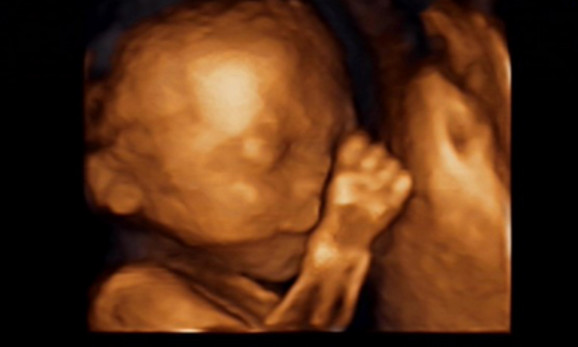

27岁的曹女士,已经怀孕六个月了。三天前,“孕味十足”的她,在丈夫的陪同下来到医院,准备进行提前预约好的四维彩超检查。但是万万没想到,检查结果让她的心情一下跌入低谷!通过影像显示,胎儿嘴唇中间竟然有一指宽的裂痕。经过医生再次仔细确认,腹中的胎儿确实患有唇腭裂,也就是“兔唇儿”。

唇腭裂患儿,是因为牙槽突间骨组织的缺失,造成上颌牙弓的完整性丧失,鼻基底部塌陷,牙槽突裂隙部恒尖牙萌出受阻。胎儿出生以后,需要通过牙槽突植骨术来完成唇部整形。手术具体怎么做,什么时候做,要做几次,这些都要根据孩子的具体病情。至于是否要生出来,这个就要由孕妇及家人自己决定。